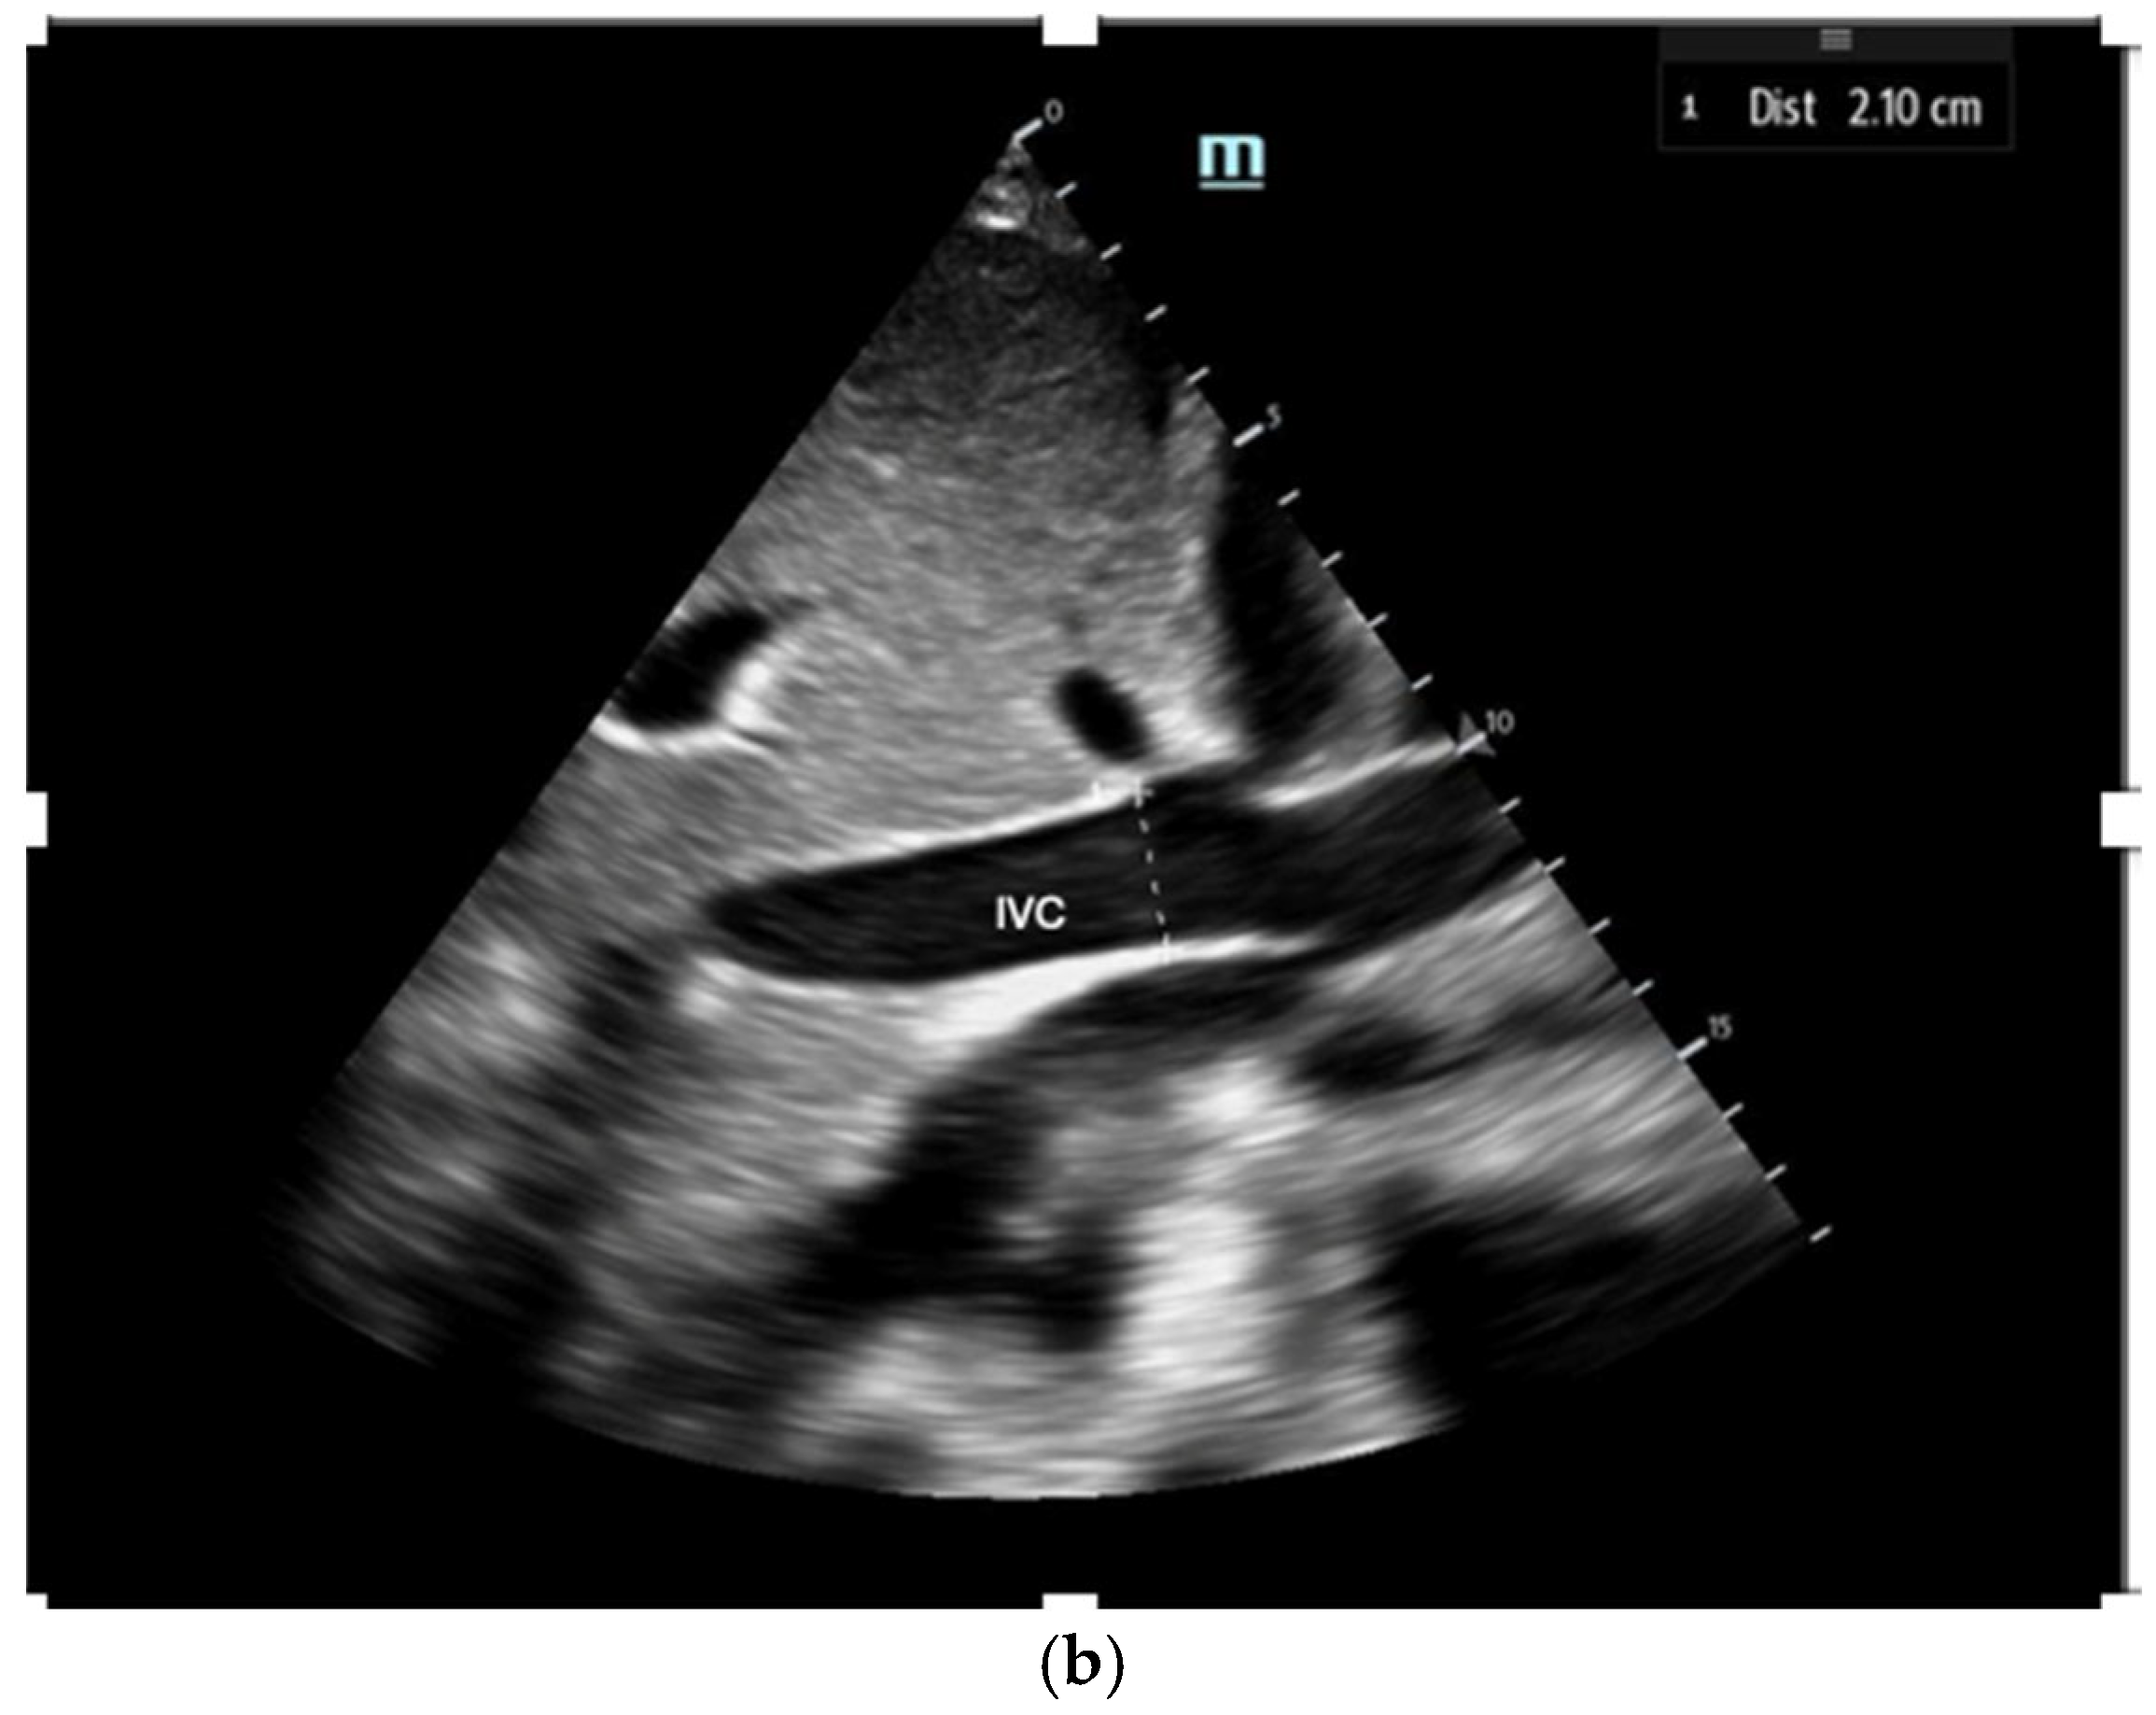

1. Inferior vena cava assessment: The ultrasound assessment of IVC size and collapsibility offers a non-invasive method to evaluate CVP and RAP (Figure 2). The IVC’s diameter varies with CVP and intravascular volume, although factors like positioning, respiratory variation, and intrathoracic pressure may also influence IVC size [17]. Studies show a strong correlation between maximum IVC diameter (IVCmax) and invasive CVP measurement, with the 2018 ASE guidelines recommending measuring IVCmax during expiration [17]. The IVC compressibility index (IVCCI), which is a dynamic hemodynamic measurement incorporating maximum and minimum IVC diameter (taken at expiration and inspiration, respectively), also has a strong negative correlation with CVP (Figure 2)

Figure 2.

The IVC (Inferior Vena Cava) diameter measured in subcoastal view approximately 1 cm below IVC–hepatic vein junction in a spontaneously breathing person during both inspiration (a) and expiration (b).